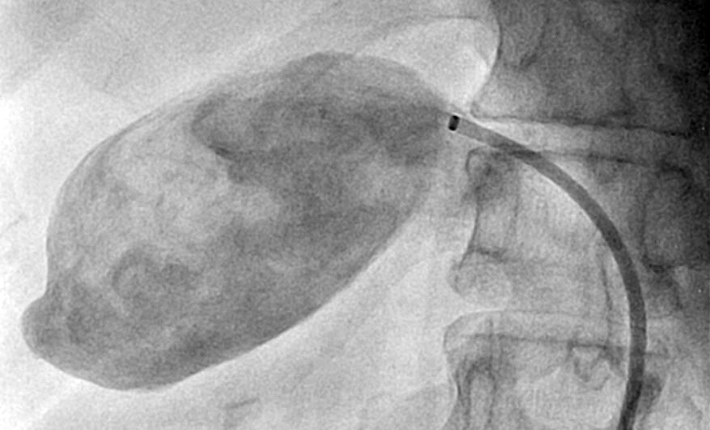

Neste boletim informativo, dr. Marcelo D´Anzicourt Pinto e dr. Guilherme Evangelista Rezende nos trazem revisão de literatura sobre a etiologia, apresentação clínica, diagnóstico por imagem, história natural e principalmente comentam os recursos atuais para intervenção não cirúrgica com materiais especificamente selecionados para tratamento percutâneo de aneurismas de artérias viscerais. Assim, dr. Marcelo mostrou caso de fechamento de aneurisma de artéria renal com técnica de utilização de Coil e Stent associadamente e que foi realizado no setor de Hemodinâmica da Santa Casa de Ribeirão Preto (SP). E o dr. Guilherme fez o tratamento intervencionista na Santa Casa de São Sebastião do Paraiso (MG) de grande aneurisma de artéria hepática utilizando outro tipo de dispositivo onde a oclusão do colo aneurismático garantiu a exclusão da grande dilatação vascular e garantiu a perviedade distal da artéria relacionada. Finalmente, dr. Antonione Lamartine faz completa análise das etiologias e das estratégias antitrombóticas em diferentes cenários clínicos onde a carga trombótica coronariana demanda abordagens individualizadas na sala de hemodinâmica bem como terapias fibrinolíticas adjuntas. Esperamos que tenham leitura informativa a sua prática clínica.

Aneurisma de artéria renal; do diagnóstico ao tratamento endovascular